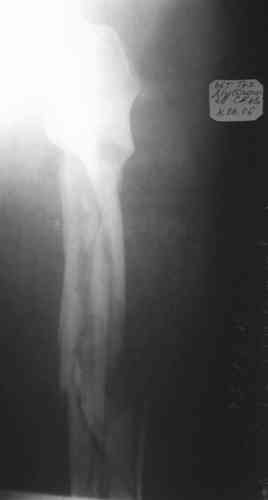

Уважаемые коллеги! Пришел на консультацию вот такой больной (первые 3-и рисунка). Травма автодорожная, апрель 2006г. Лечился консервативно, вытяжение и гипс. Через пять месяцев стал ходить. Укорочение бедра 6 см. 26 февраля 2007г. оступился, упал. Прооперирован в г.Баку - наложен стержневой аппарат. Ходит с костылями, наступая на левую ногу.

Мы попросили что нибудь из ранних снимков. Принес рентгенограммы перелома (рис. 4,5). Посмотрели, наснимали сами (рис. 6-10). Похоже, что нет сращения нигде. Хотелось - бы обсудить следующие вопросы: 1. дальнейшая тактика - реостеосинтез или подождать (ослабить аппарат, дать нагрузку и т.д.)? 2. если реостеосинтез - то чем и как? Юрий Алексеевич Булахтин